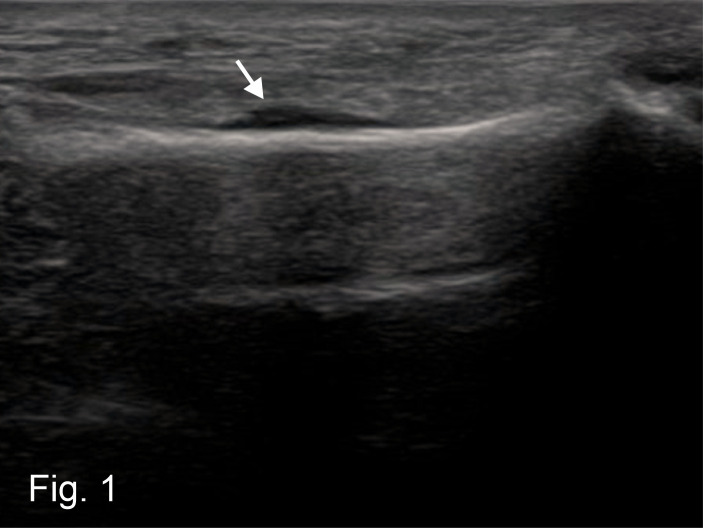

The early diagnosis of stress fractures is a challenge in daily primary care practice. Point of care ultrasound (POCUS) can be helpful in the diagnosis of early signs of an incipient stress fracture. A 52-year-old woman presented with a history of chronic overuse in the left forefoot. A sonographic examination in the area of the reported pain point on the third metatarsal (consistent with a marching fracture) showed a clear accumulation of fluid, corresponding to subperiosteal hematoma. After only two weeks of resting the forefoot, a repeat examination using POCUS showed clear callus formation. This confirmed the suspected diagnosis of an early stage stress fracture. This case shows a sensible and easy-to-learn way of using POCUS in general practice. POCUS in combination with clinical examination and anamnesis is a cost-effective and timely diagnostic option without radiation exposure.